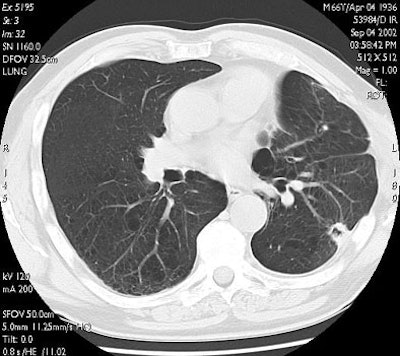

![]() |

| RF ablation of stage IA non-small cell lung cancer (NSCLC). Above: Pretreatment CT scan shows solitary small NSCLC of left lower lobe. Below: At CT obtained one month after RF ablation, a ground-glass density ablation zone replacing the lesion and 1-cm of surrounding pulmonary parenchyma is detected. Images courtesy of Dr. Riccardo Lencioni. |

| In the same patient, CT studies performed three months (above) and six months after treatment (below) show progressive shrinkage of the area of coagulation necrosis that exhibits central cavitation. No signs of tumor recurrence are detected. Images courtesy of Dr. Riccardo. |